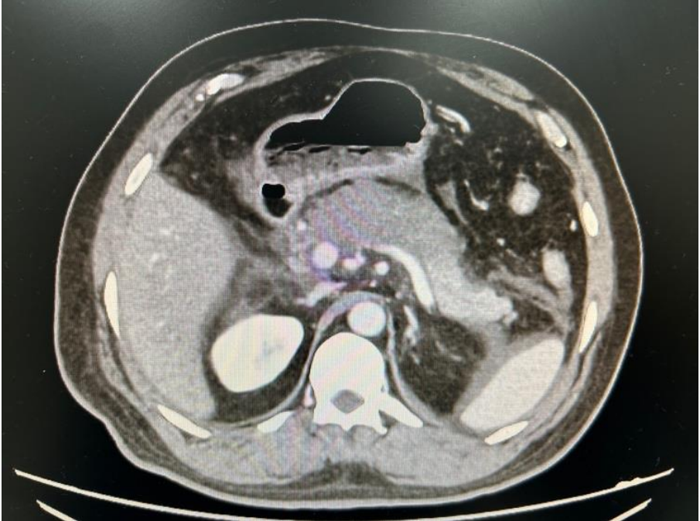

Realizada tomografia computadorizada para diagnóstico diferencial e obtida a imagem abaixo: